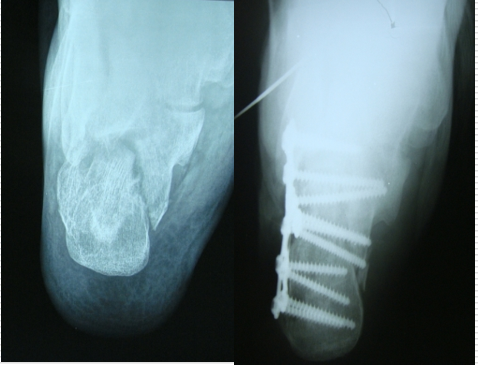

技巧六、如何恢复跟骨的宽度对于Sander‘s分型Ⅳ型骨折,外侧壁膨出,跟骨增粗明显。这时可以用简单的暴力给予复位-----锤击

它带来的额外收益是:跟骨体部的骨质缺损间隙消失,而不必植骨。

在放跟骨板之前,用击锤锤击跟骨外侧壁,恢复跟骨宽度。此时应保持克氏针在维持正常的复位位置

它带来的额外收益是,跟骨体部的骨质缺损间隙消失,而不必植骨。

技巧八、是否需要植骨,以及取髂骨方法在放跟骨板之前,用击锤锤击跟骨外侧壁,恢复跟骨宽度。它带来的额外收益是,跟骨体部的骨质缺损间隙消失,而不必植骨。如果一定要植骨,可以劈开髂骨,保留内外板,只取板障内的松质骨。